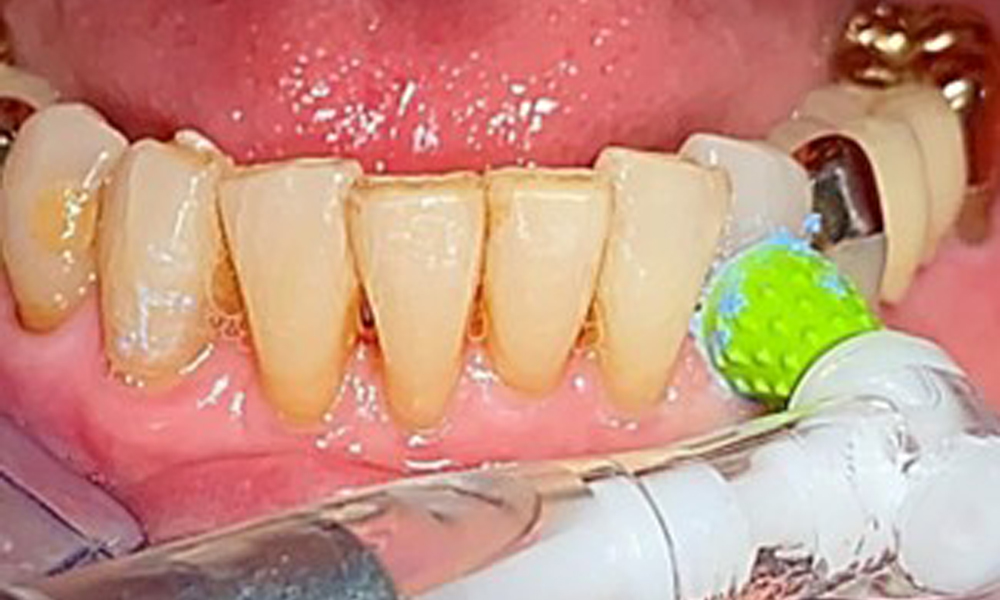

A single-tufted brush is specifically recommended for the telescopic prostheses (Fig. 8) and the patient should be advised on the appropriate interdental brush size (Fig. 9). The patient has been implementing these recommendations for intraoral hygiene at home for many years and was encouraged to continue during the professional preventive dental appointment.

An air polishing system should be used with low-abrasive powder to remove biofilm from the restoration margins, interdental areas and implant surfaces (Fig. 12). Selective polishing (Fig. 13) should be used to smooth any less sensitive areas, as this decreases bacterial reattachment (9).